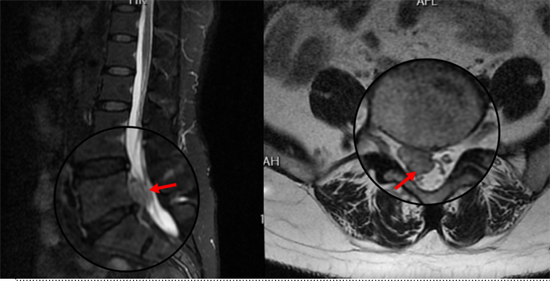

術后復查MRI顯示脫出椎間盤完全摘除,

神經(jīng)松解徹底,患者術后恢復良好